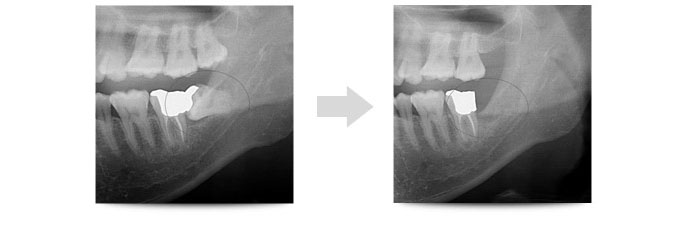

院長である私は大学の口腔外科に勤務しておりましたので「親知らずの抜歯」は得意とする分野となります。まずはしっかりお口の中の診査診断を行います。通常はレントゲンで状態を確認しますが、ケースによってはCT撮影も行い状態を確認します。

以下は当院で実施した難しい親知らずの抜歯症例となります。

水平埋伏歯とは、完全に横向きにはえている歯を指します。通常通りにまっすぐはえている歯よりも抜歯が難しい状態です。

水平埋伏歯を抜歯するためには、歯茎を切開してめくりあげ、歯の頭の部分と骨の一部分を削り取り、分割しながら抜歯していきます。